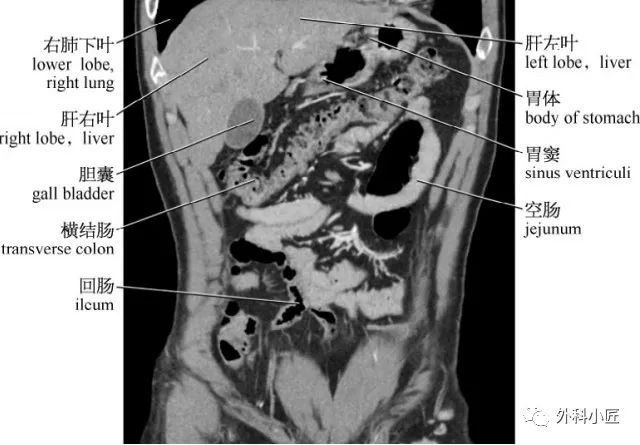

46组对比图带你完全掌握腹部影像解剖_医学界-助力医生临床决策和职业